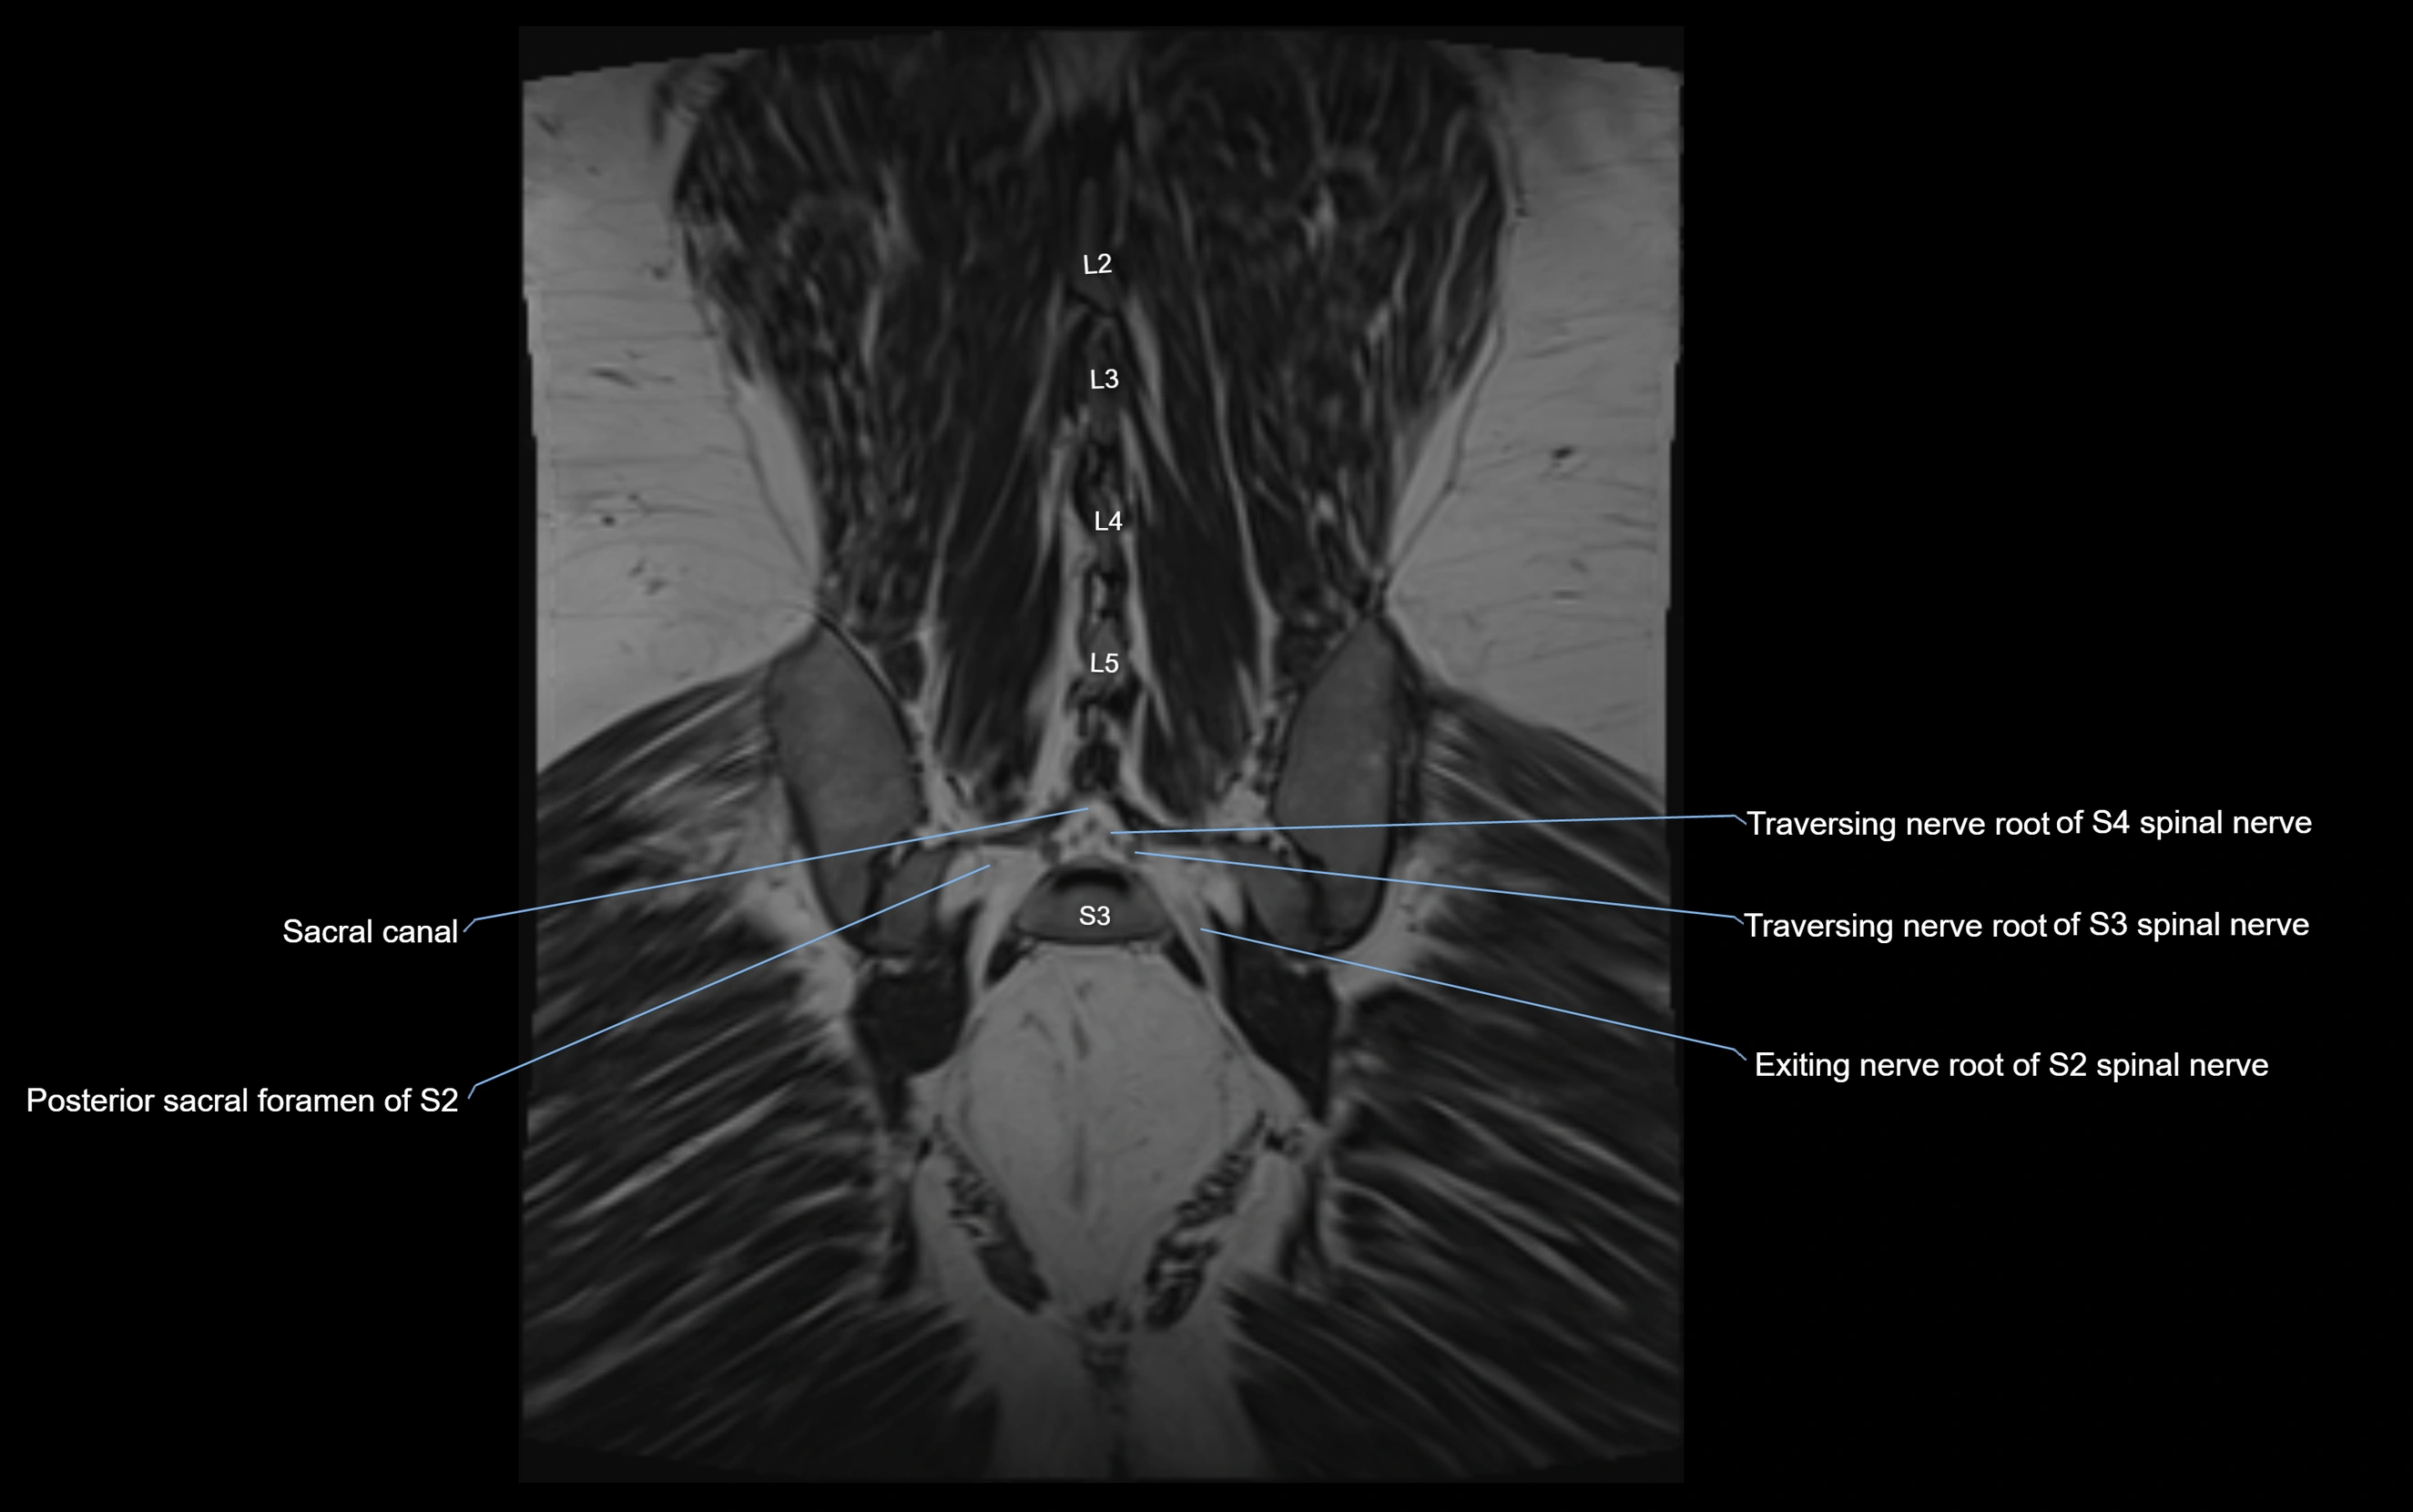

MRI image

image